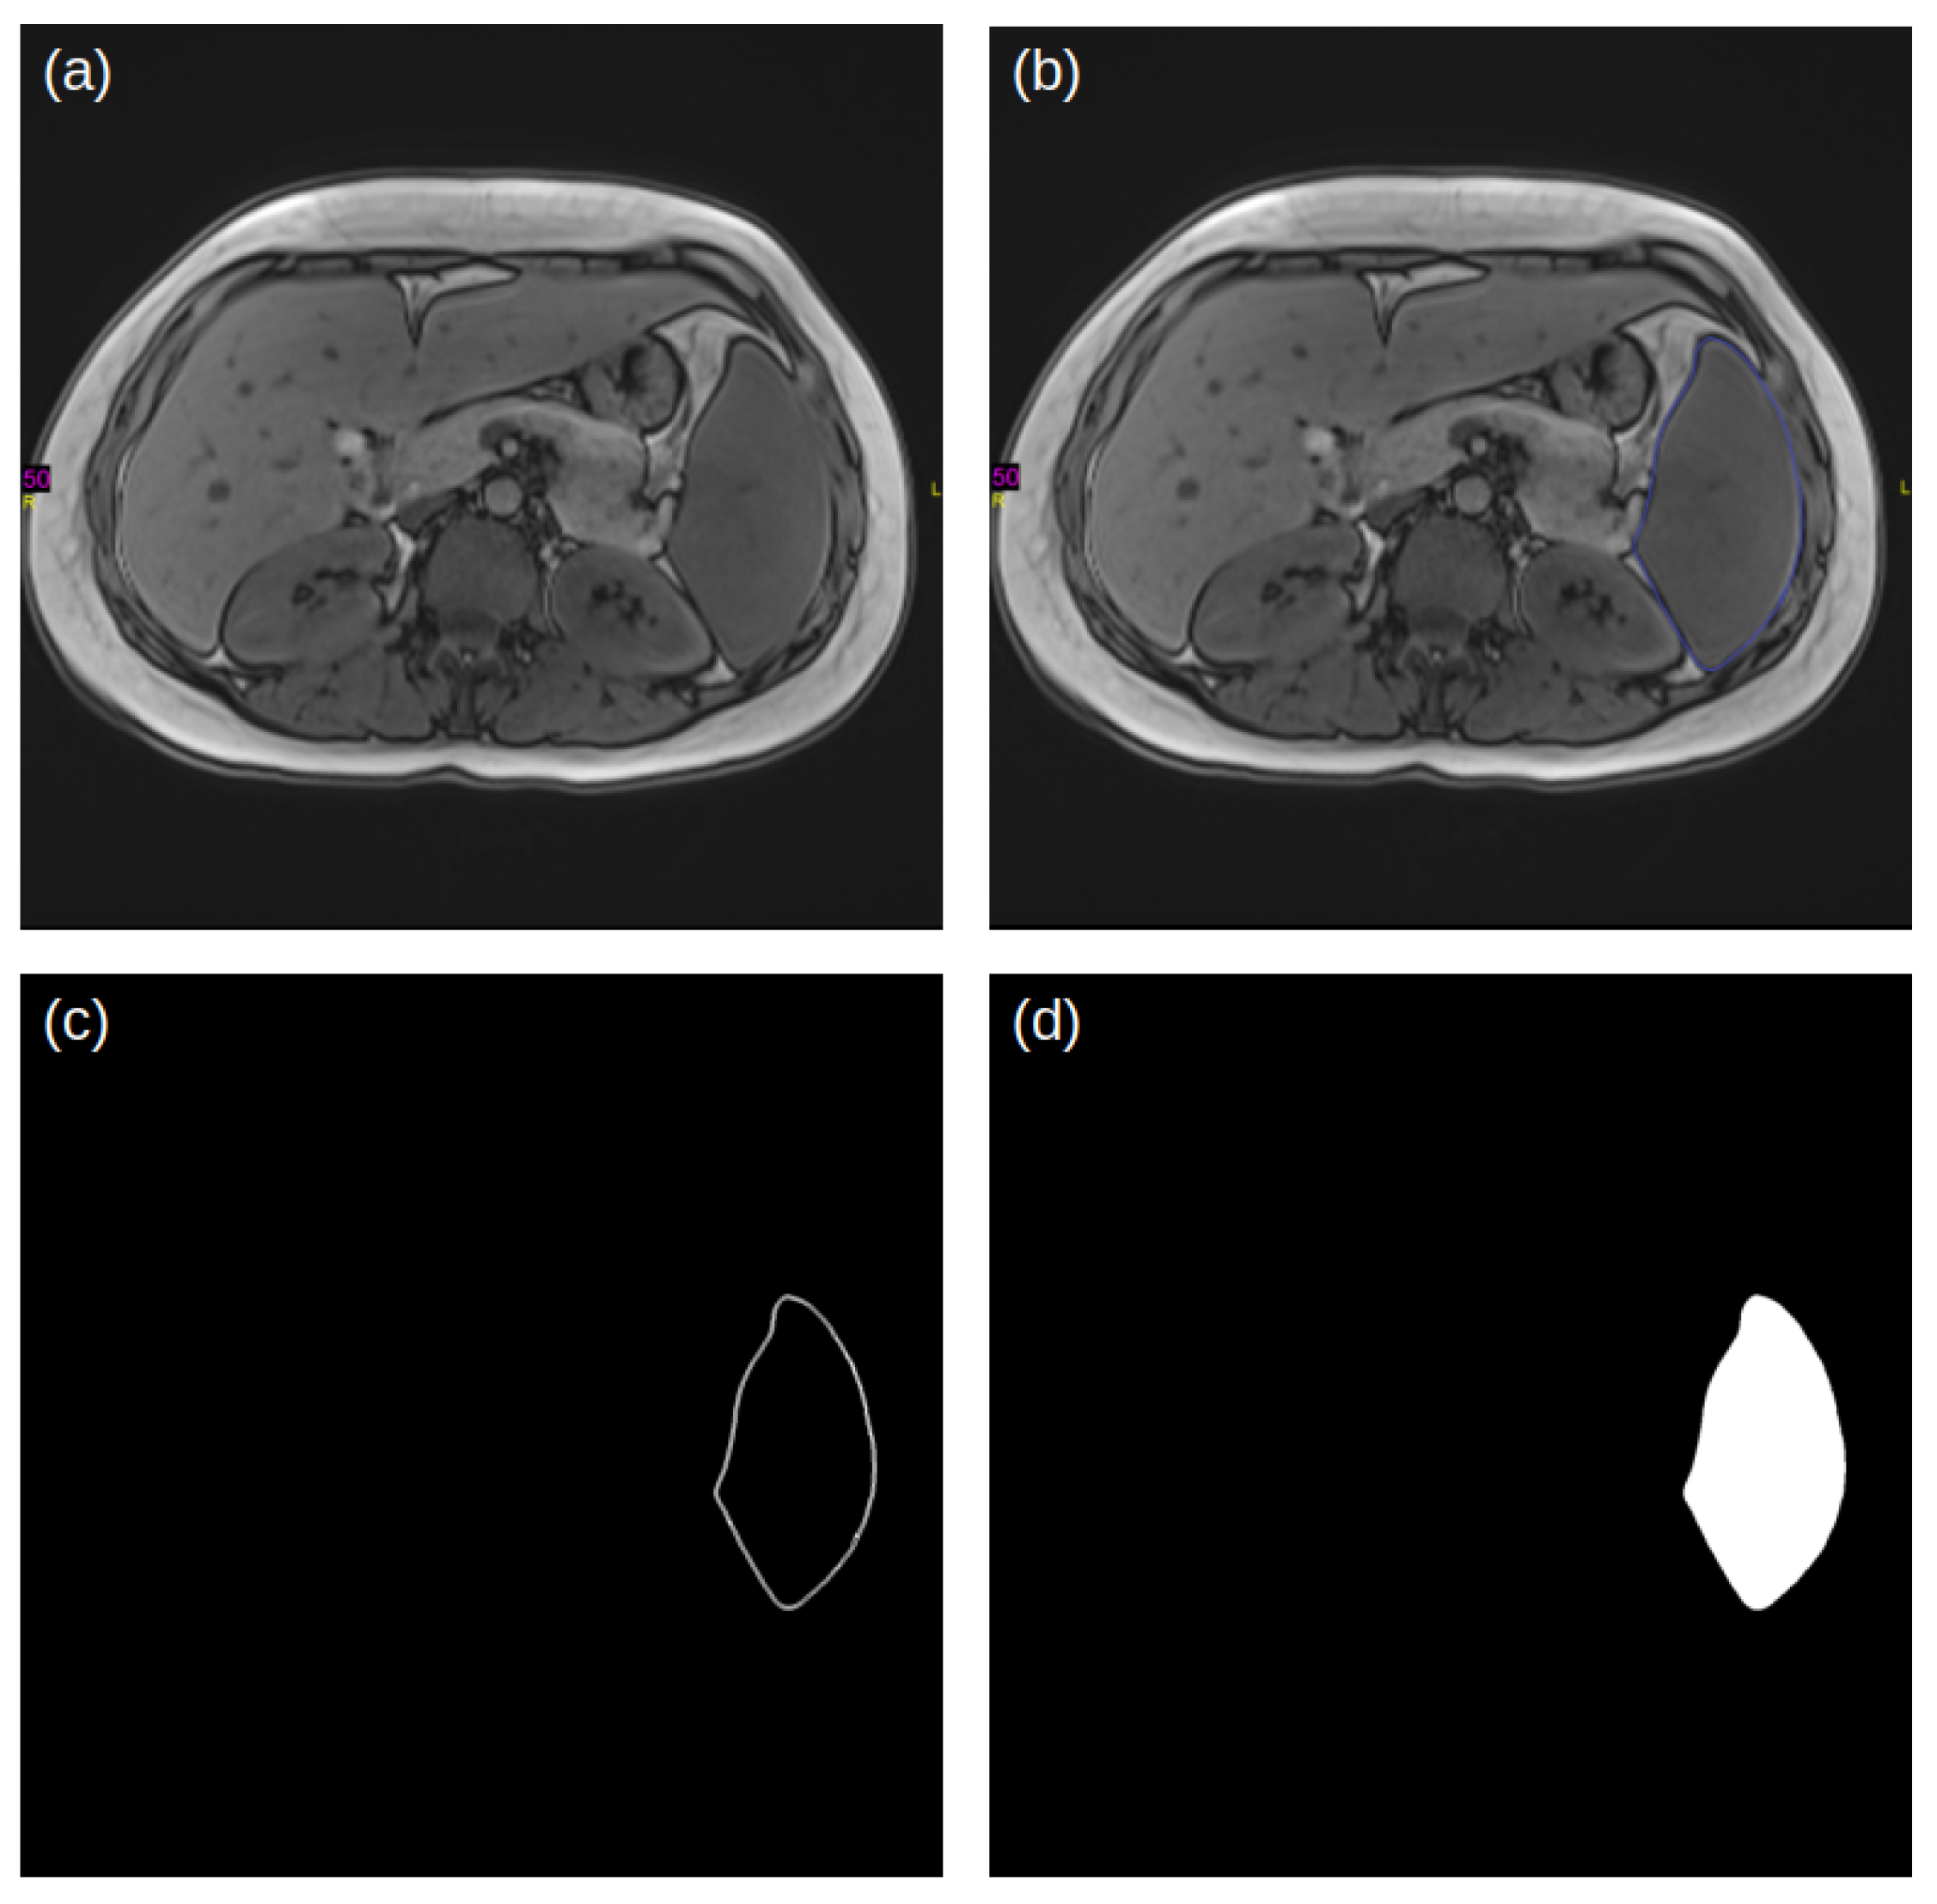

2.2. Reference Labeling and Dataset

2.3. Pre-Processing

2.4. Deep-Learning Modeling for Automated Segmentation